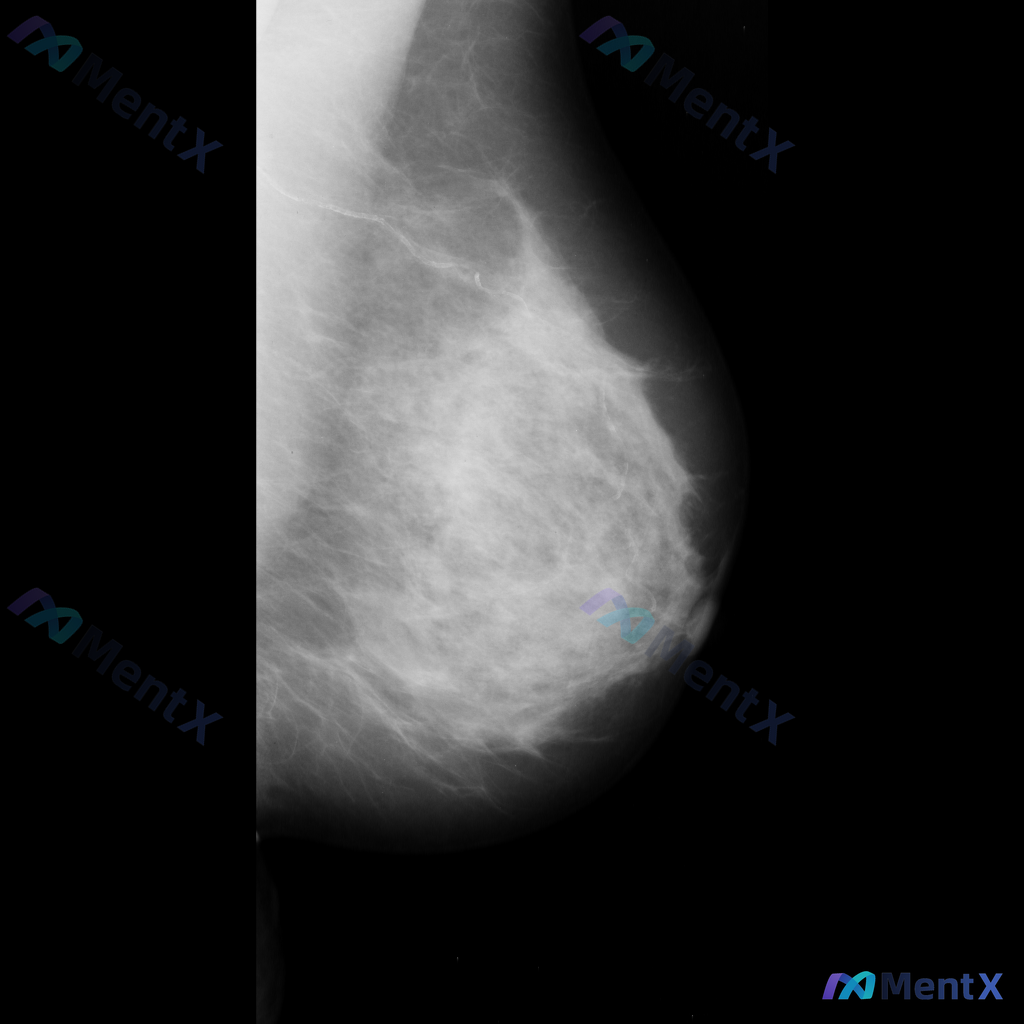

整理到一份右侧乳腺内外斜位钼靶X光片的影像资料,大家可以一起讨论下: - 影像中可见散在的纤维腺体密度,密度较高 - 发现多发斑点状或细小钙化点,分布散在,目前倾向良性特征 - 另有局部模糊的不对称致密影,与背景腺体组织融合,未见明确毛刺或结构扭曲等恶性特征 单看这份影像描述,大家会优先考虑什么方向...